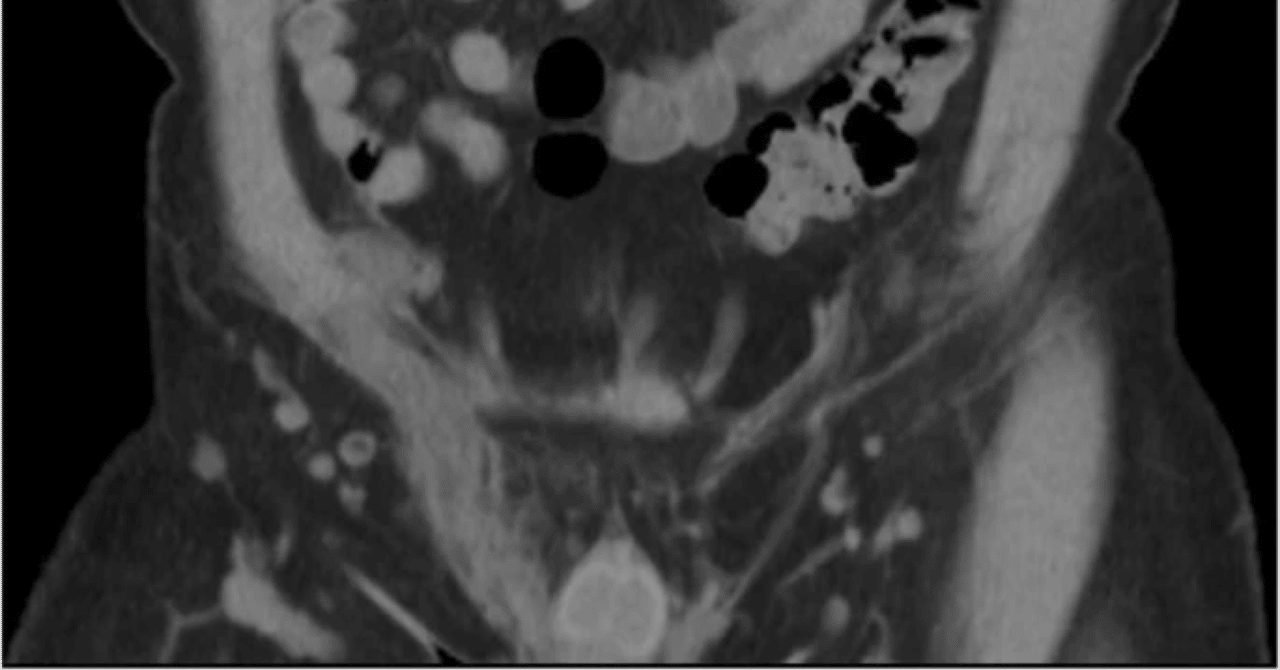

漠然とした背部または下腹部(陰茎、陰嚢、腹膜)の痛み、射精時痛、血精液症、血尿、排尿時の刺激感や閉塞感、勃起不全などが出現する。感染症は、性感染症や前立腺生検などの処置の合併症による場合がある。大腸菌、黄色ブドウ球菌、連鎖球菌、淋菌、結核菌などが原因菌となる。通常は抗生物質で治療する。不快感が続く場合は、経尿道的精嚢鏡検査が考慮される。感染が膿瘍化した場合は、皮膚からのドレナージや手術が必要になる場合がある。結核、住血吸虫症、エキノコックス症による精嚢炎の場合は、基礎疾患に応じて調査、診断、治療する。